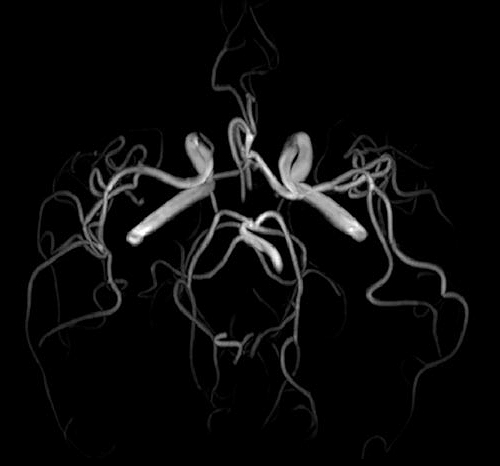

Ο Magnetom Lumina διαθέτει πολυκάναλα πηνία τελευταίας τεχνολογίας για υψηλής διαγνωστικής αξίας απεικόνιση της ανατομίας και της λειτουργίας όλων των περιοχών του ανθρωπινου σώματος. Διαθέτει δυνατότητα πραγματοποίησης όλου του φάσματος των εξετάσεων Μαγνητικής Τομογραφίας, όπως νευρολογικών, ογκολογικών, μυοσκελετικών, καρδιολογικών εξετάσεων, καθώς και ειδικές εξελιγμένες τεχνικές απεικόνισης. Κάποιες από αυτές της ειδικές εξετάσεις είναι ολοσωματική μαγνητική τομογραφία, τεχνική μείωσης παρασίτων από συμβατά με μαγνητικό τομογράφο μεταλλικά εμφυτεύματα, παραμετρικοί χάρτες καρδιάς για διάγνωση αρχόμενης ισχαιμίας, στεφανιογραφία χωρίς έγχυση σκιαγραφικού, μελέτη αιμάτωσης εγκέφαλου, πολυπαραμετρική προστάτη, μαγνητική μαστογραφία, μέτρηση αιμάτωσης εγκέφαλου, μέτρηση σιδήρου και λίπους του ήπατος, δυναμική αγγειογραφία.

Απεικόνιση 2